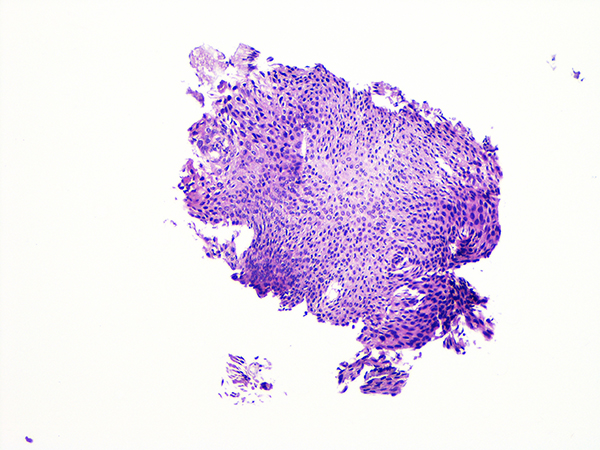

![]() Case 2

Soft Bx CIN 2 10x - Low Power |

Soft Bx CIN 2

40x - High Power